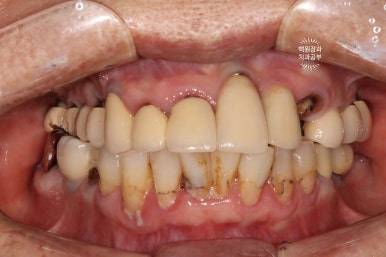

처음 오셨을 때 정면 사진입니다.

잘 보시면, 아까 보였던 치과용 파노라마 사진대로 뿌리만 남은 두 개의 치아를 찾아보실 수 있으실거에요. ㅎㅎ

제가 서두에서 어금니에 스트라우만 임플란트가 많다고 말씀드렸는데, (나머지도 branemark 제품으로 보이며, 명품으로 주름잡던 스웨덴 임플란트 입니다.) 이 미친 퍼포먼스의 스위스 임플란트는 20년이 지난 지금도 짱짱한 성능을 자랑하고 있답니다.

사실 구강위생관리가 그렇게 완벽하신편이 아니신데도.. 이런 임상결과를 보이고 있는 것이 늘 경이롭습니다.

아까 말씀드렸듯, 왼쪽 위 송곳니와 오른쪽 아래 작은어금니에 뿌리만 있는 잔존치근이 관찰됩니다.